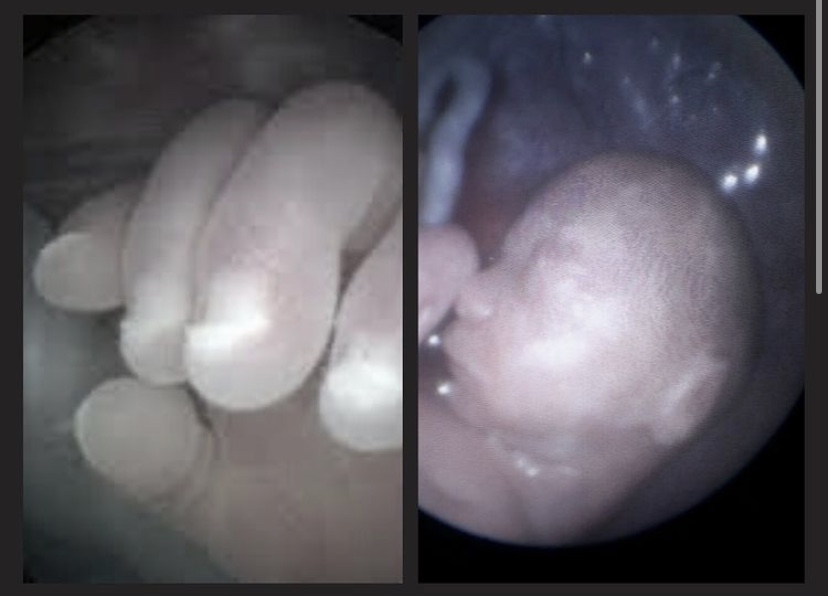

קמתי הבוקר עם הפרשה דמית מועטה

החלטנו לא לנסוע בשבת ועכשיו אסע להיבדק

אני שבוע 10 ומתפללת שהכל בסדר.

כל היום נחתי שכבתי המיטה ושתיתי הרבה ובאמת אין כאבים או עוד הפרשות דמיות.

אני זקוקה לתפילות ובעזרת ה שהכל בסדר עם העובר.

הלוואי שזה סתם ורק משהו חד פעמי.

הריונות קודמים בהתחלה היו לי כאלו הפרשות כבר חשבתי שהפעם דילגתי על השלב הזה והסבל של הבחילות היה מספיק צער.

מתפללת כל כך שהכל תקין.

מחכה להבדיל ולברוח למוקד נשים

מעדכנת!!!הריון חדש..

ברוך ה׳!!!! יופי העיקר תנוחי ואם תשכבי מה טוב העיקר שתנוחי❤️anonimit48